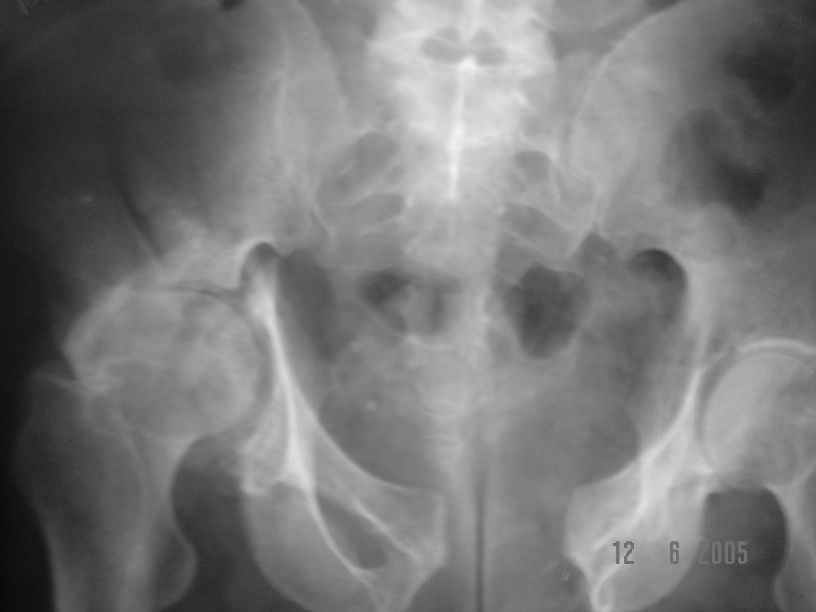

Dear All, The patient came to us for opinion regarding this # of pelvis which he sustained 5 months back.

He gives history of being on skin traction for 3,5months. After that he was advised partial weight bearing to be graduated to full weight bearing. Now the patient has difficulty in weight bearing as it is painful. He can walk a few steps only with the help of a walker. Hip movements are restricted and painful. Fl-90* ER-10* IR-0, shortening-4cm. He also had # of humerus and radius/ulna, which were plated and have united. The serial x-rays of the pelvis/Hip during these 5 months show that the hip joint has been in the same position. I have the CT pictures also but not digitalized as yet.

He is 47 years old, Class-1 officer.What are the options? Expert comments please.1. # Pelvis stabilization - Is it possible at 6 mths? And subsequently THR.

2. THR in this position- Cup positioning in a deformed pelvis?

It is a displaced and ununited fracture of the acetabulum, probably type C (AO). The pelvis is not fractured from what one can see of the sacro iliac joint.

Sorry missed the wide open pubic diastasis.

You could tryan open reduction of the pubis through a Pfannensteil inscision and get some closure done. An external fixator may help preoperatively to get some compression.